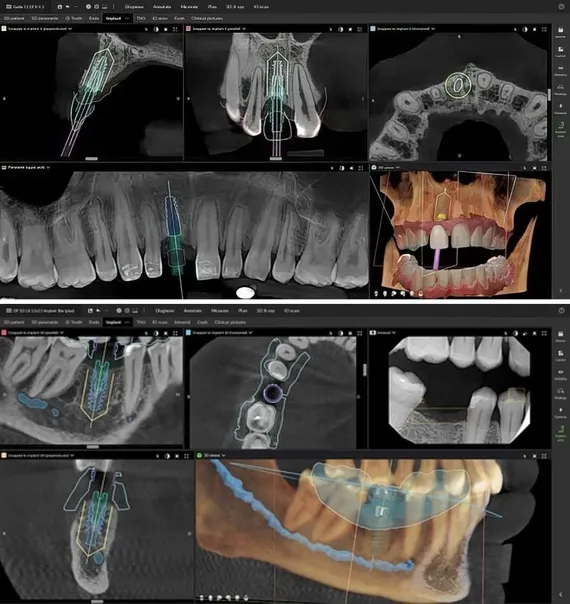

Traditional dental X-rays provide a flat, two-dimensional image. CBCT captures a three-dimensional view of the jaw, teeth, and surrounding structures, allowing for more accurate diagnosis and treatment planning.

Panoramic X-rays (PANO) and Cone Beam Computed Tomography (CBCT) are both diagnostic imaging tools, but they differ significantly in the level of detail and clinical application:

• Panoramic X-rays provide a flat, two-dimensional image of the jaws, teeth, and surrounding structures. It is useful for general evaluations like tooth positioning, impacted teeth, or jaw relationships.

• CBCT scans capture a three-dimensional image that allows us to view structures from multiple angles and cross-sections. This is essential for precise treatment planning, especially for procedures like dental implants, periodontal surgery, impacted teeth, or pathology evaluation.

In short: PANO offers a broad overview, while CBCT delivers highly detailed, 3D insight — ideal when precision matters.